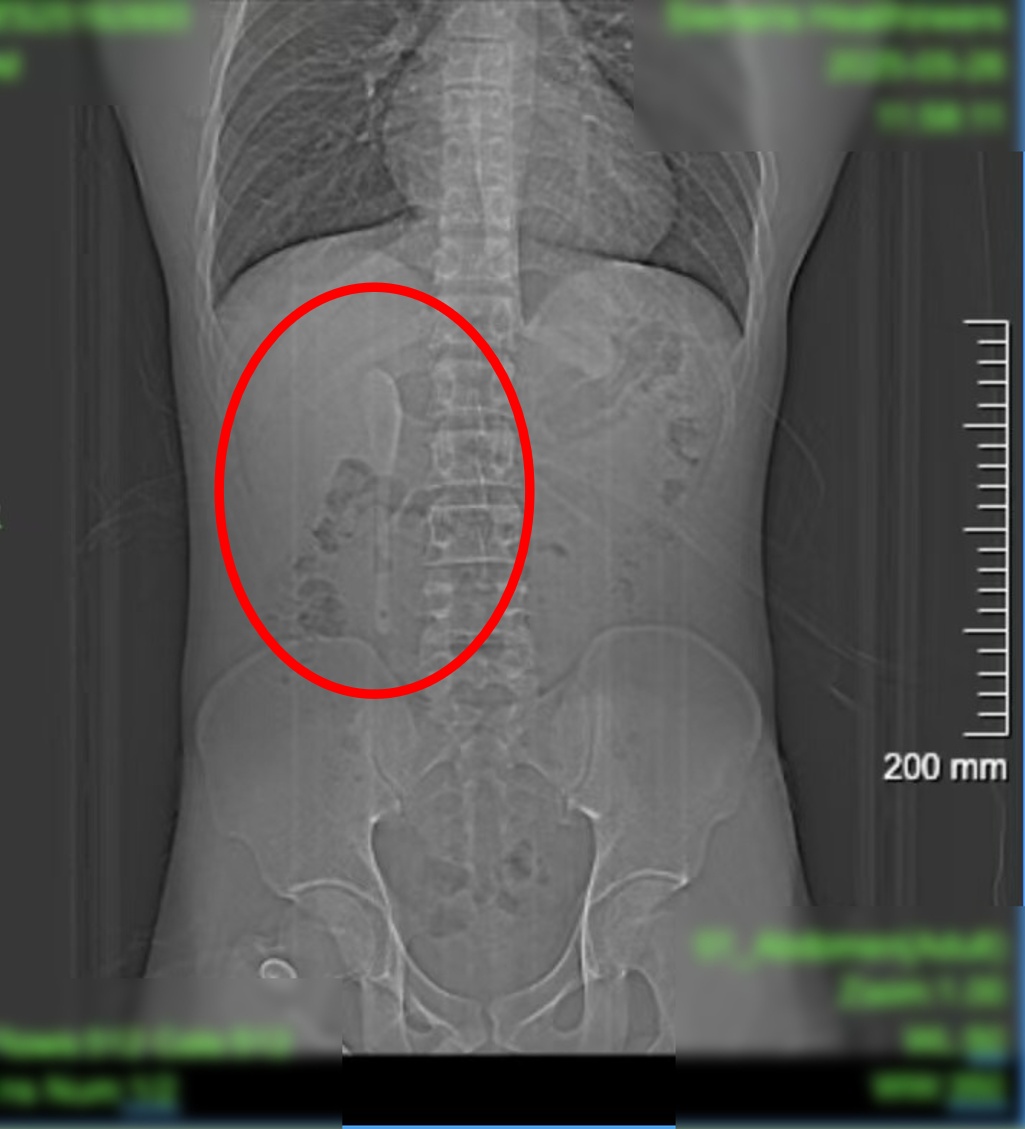

CT显示,这支近15厘米长勺状物体,严丝合缝地横亘于十二指肠球部与降部交界的生理狭窄处,稍有不慎即可能刺穿肠壁,引发腹膜炎或大出血。

中山医院内镜中心主任周平红教授表示,此处腔隙狭窄且肠壁极为菲薄,异物极易嵌顿,稍有不慎容易造成穿孔。

昨天(6月18日)下午,小言被推进内镜手术室。虽然医护团队对手术难度有所预判,但内镜画面仍让团队倒吸凉气——勺子的“头”卡在十二指肠球部,而它的“长柄”则一路延伸下去,拐了个弯卡在了更深的十二指肠降部与水平部交界处。